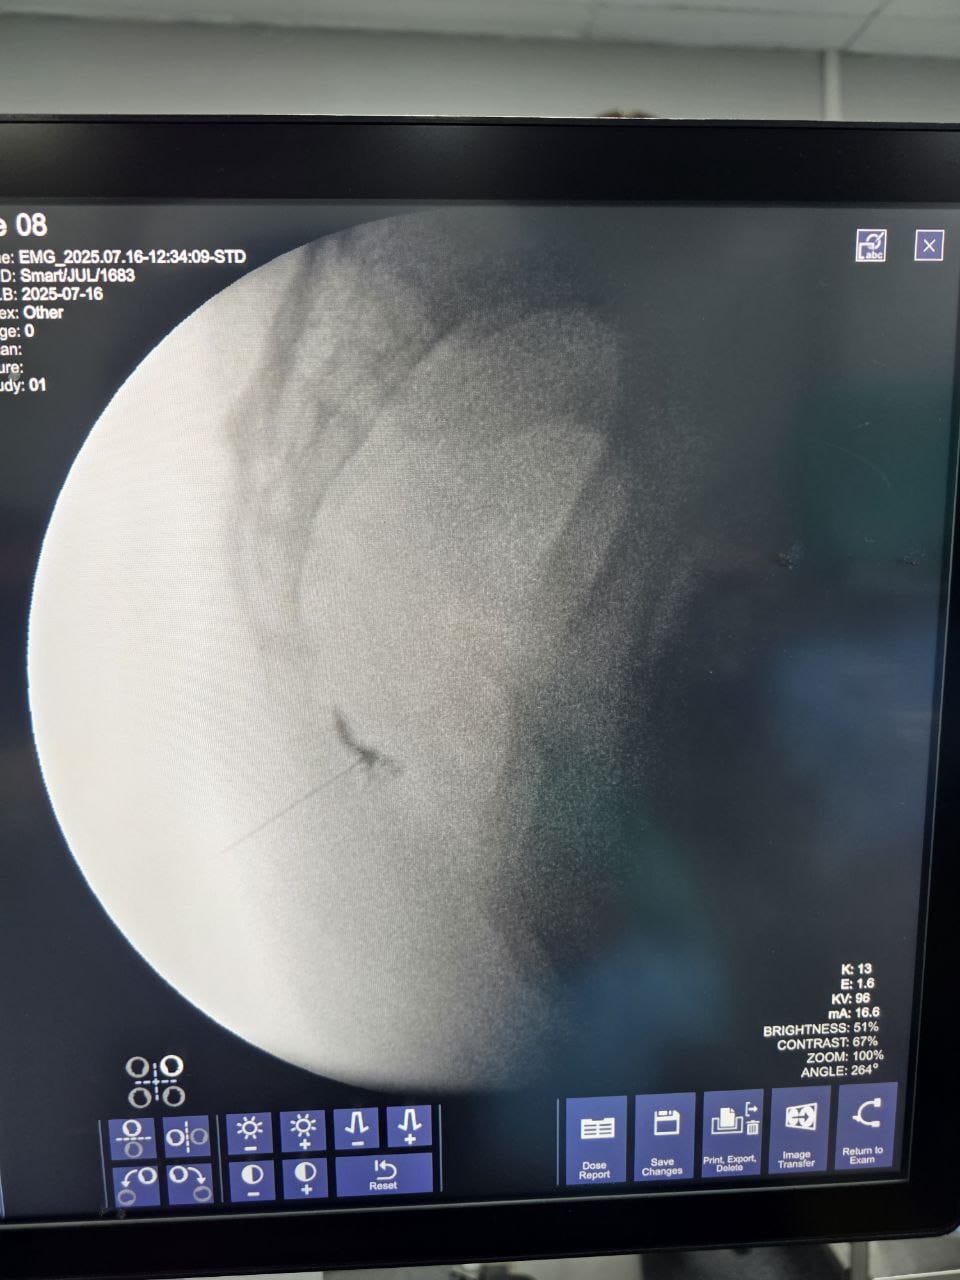

Procedures

Struggling with chronic pain? Get advanced, personalised pain management from Dr. Manish De, one of Kolkata’s leading pain specialists. From knee pain, heel pain, low back pain, frozen shoulder, migraines, cancer pain to post-TKR persistent pain—Dr. De offers safe, evidence-based treatments across multiple locations: